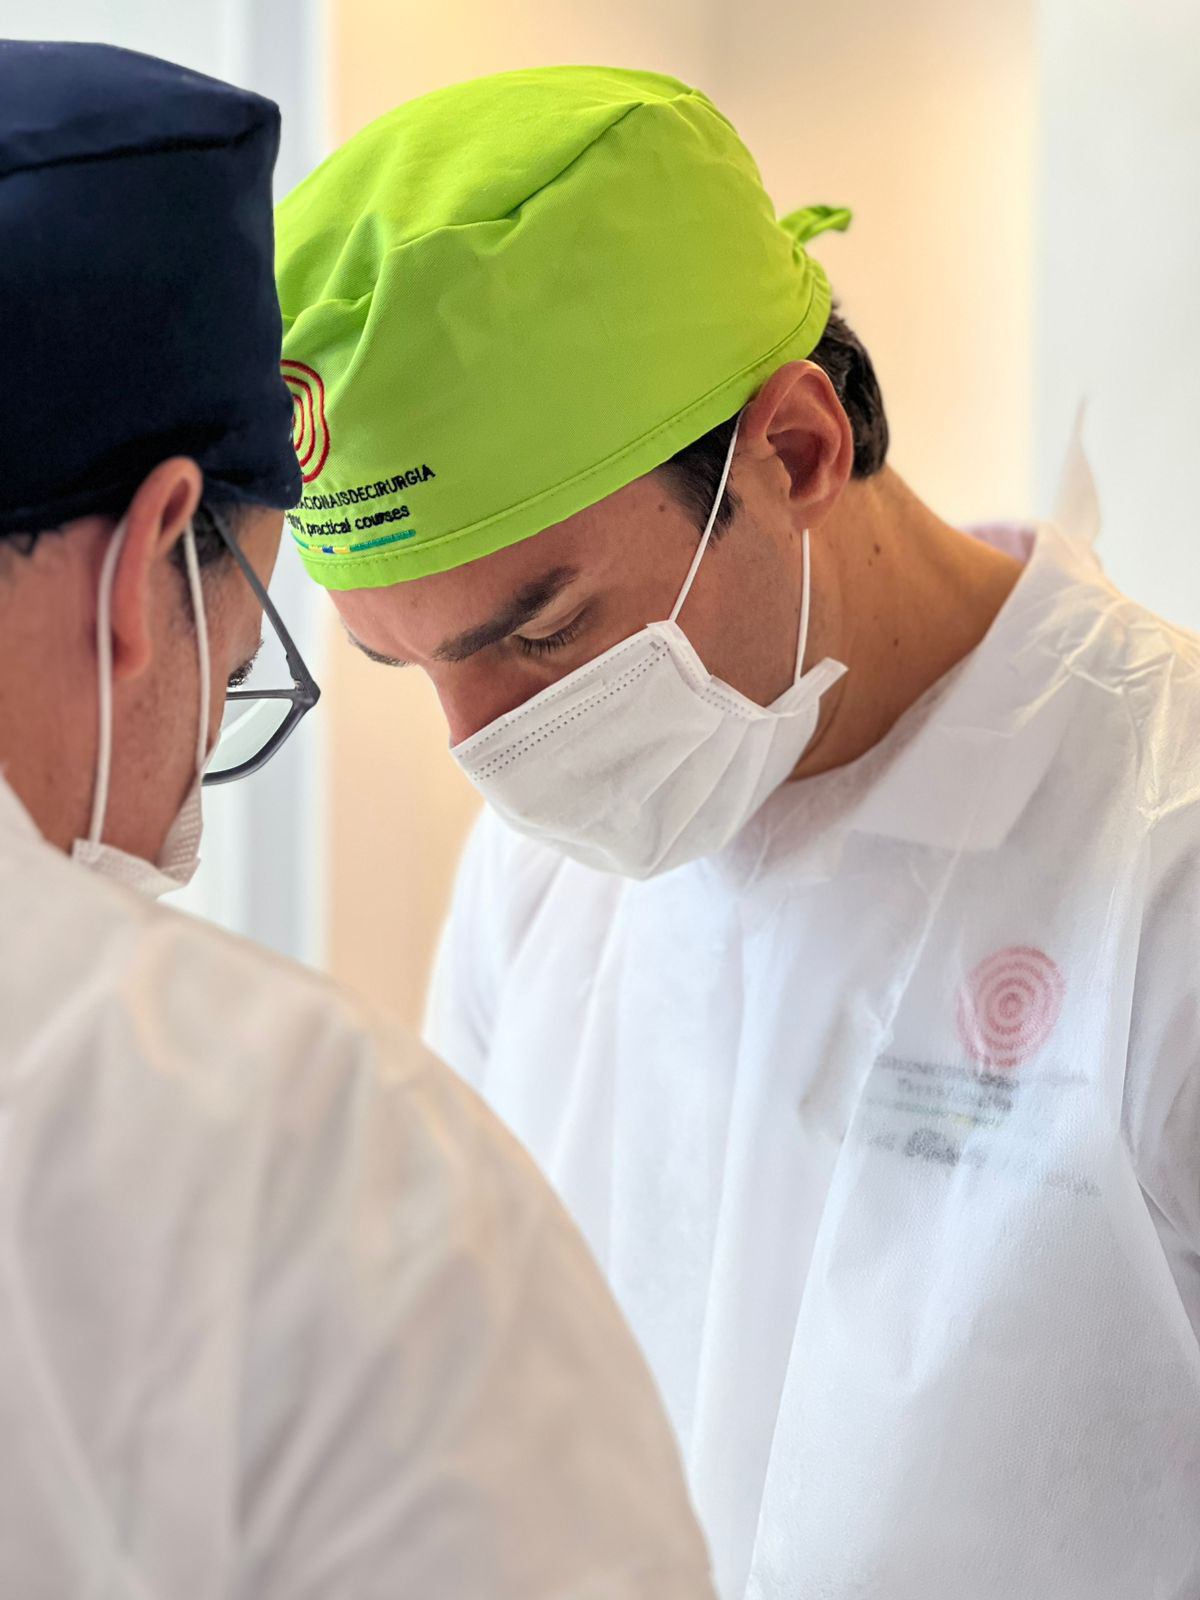

IL CORSO DI IMPLANTOLOGIA E CHIRURGIA ORALE PRATICO SU PAZIENTE IN BRASILE

ONE TO ONE

Scopri l’eccezionale opportunità formativa offerta da Cursos Internacionais de Cirurgia, il percorso ideale per chi desidera migliorare ed eccellere nella chirurgia orale e maxillo facciale

I nostri Tutor

Odontoiatra, Instancabile e appassionato di chirurgia orale, è Tutor e responsabile Italiano di Cursos Internacionais di Cirurgia.

SII TU IL PRIMO OPERATORE, SEMPRE! DALL’INIZIO ALLA FINE. IL TUO ASSISTENTE SARA’ UN TUTOR DEDICATO CHE TI SEGUIRA E GUIDERA’ PASSO DOPO PASSO NELLA RISOLUZIONE DEL CASO CHIRURGICO!